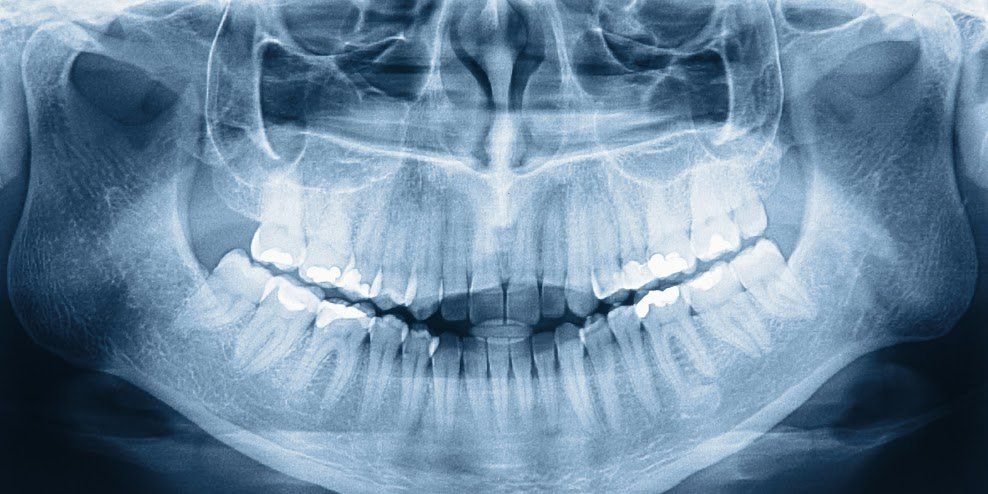

Extraoral X-rays reveal the condition of the jaw and skull, but they also show the teeth. Dentists use extraoral imagery to observe the growth of the jaw and identify impacted teeth.